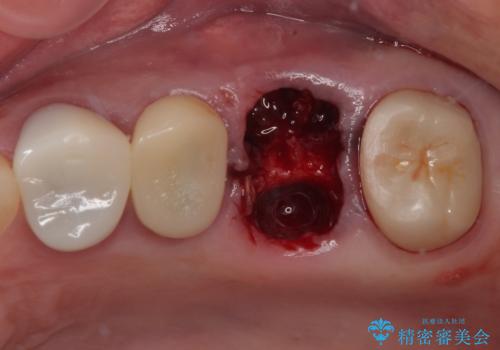

予後不良の奥歯 抜歯即時埋入インプラントによる補綴治療

- 奥歯のクラウンが土台ごと外れてしまったとのことで来院された患者様です。

保存可能ではありましたが、予後不良と患者様ご自身が判断されており、相談の結果抜歯即時埋入インプラントによる補綴治療を行うこととしました。

垂直方向への炎症が大きく、抜歯即時埋入はできたものの、即時荷重(インプラント埋入時の仮歯の装着)を可能とする安定値は得られませんでした。